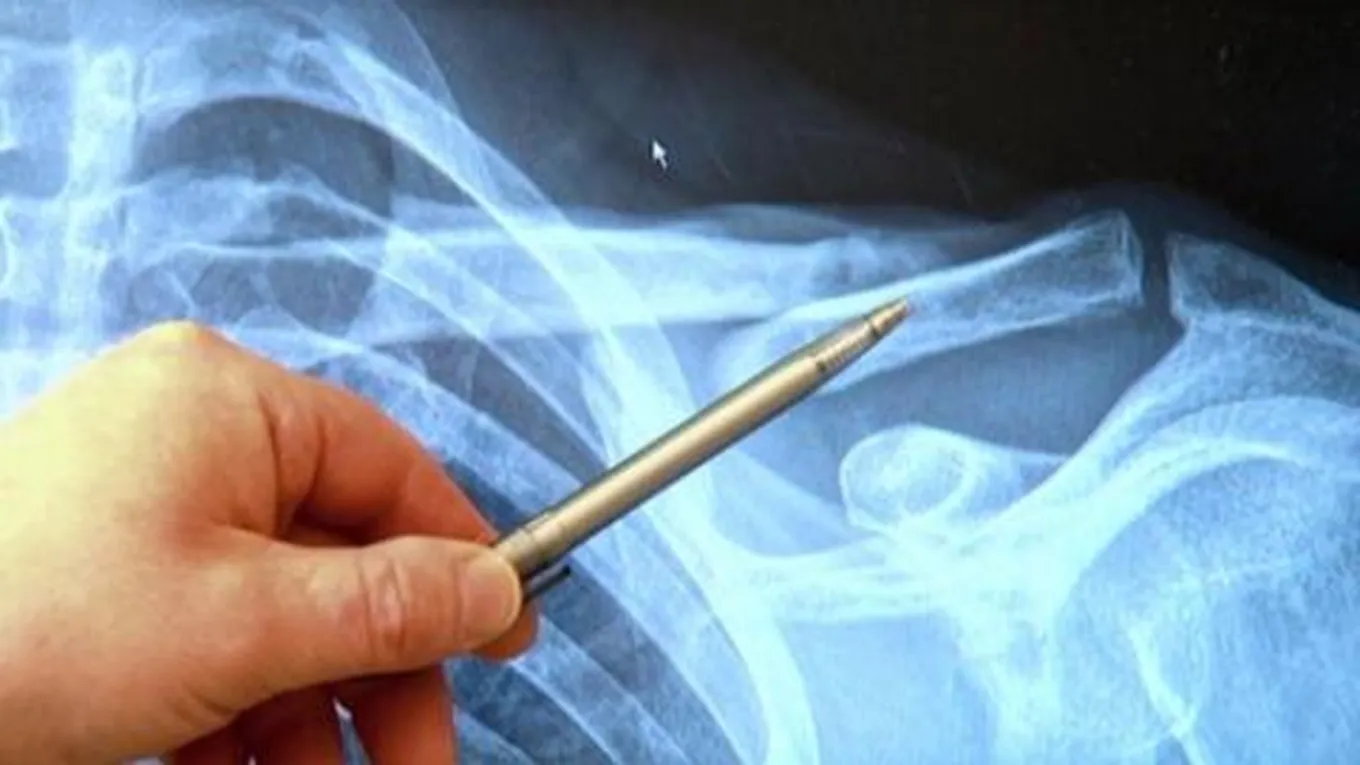

- التصوير، خاصَّةً إذا كان الألم ناتجاً عن إصابات وكسور في العظم، ويتضمَّن التصوير العديد من الخيارات، ومن ذلك:

- الأشعَّة السينيّة، حيث يتمّ تشخيص معظم الكسور باستخدام الأشعَّة السينيّة، والتي تظهر صورة للأنسجة الداخليّة، والعظام، والأعضاء، وتُعَدُّ أبسط الطرق، وأكثرها فعاليّة من حيث التكلفة.